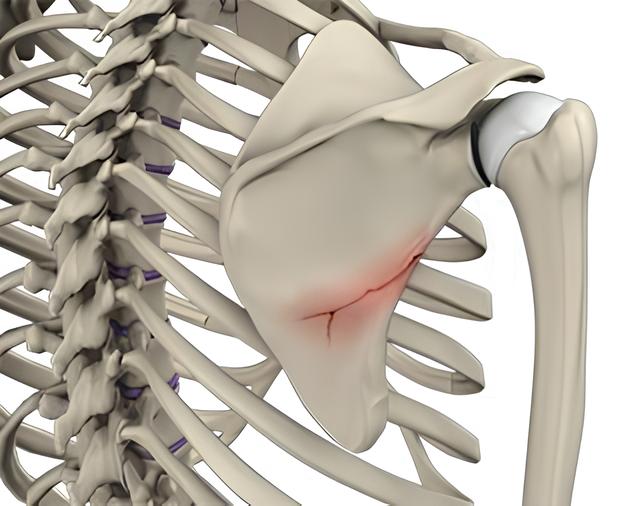

Definition Galeazzi Fracture is defined as a fracture of the distal or middle third of the radius accompanied by dislocation or subluxation of the distal radioulnar joint. It is often referred to as a “fracture of necessity” because surgical management is usually required in adults. Mechanism of Injury In children, the injury may occur with …